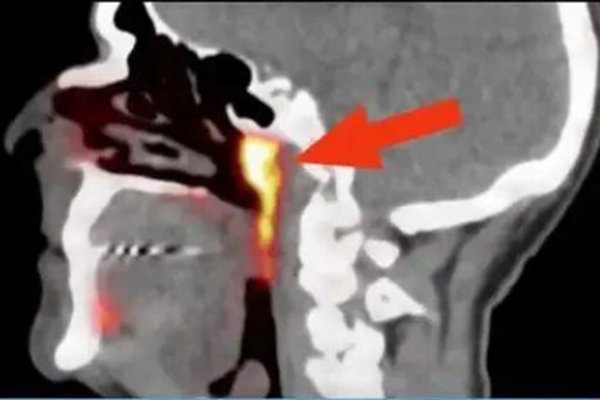

10月20日外媒报道,荷兰的一个研究癌症的研究在人体内发现了新的器官,该器官位于鼻咽里面咽鼓管隆凸的软骨上 ,据研究人员称这是一种腺体,以前人们从没有发现过。

因为其生在的部位,所以专家们给它命名为隆凸唾液腺,人类在之前只有发现了三大唾液腺分别是腮腺、颌下腺和舌下腺,现在发现这个唾液腺很可能会成为第四大,具体还需要专家们做出详细解释。